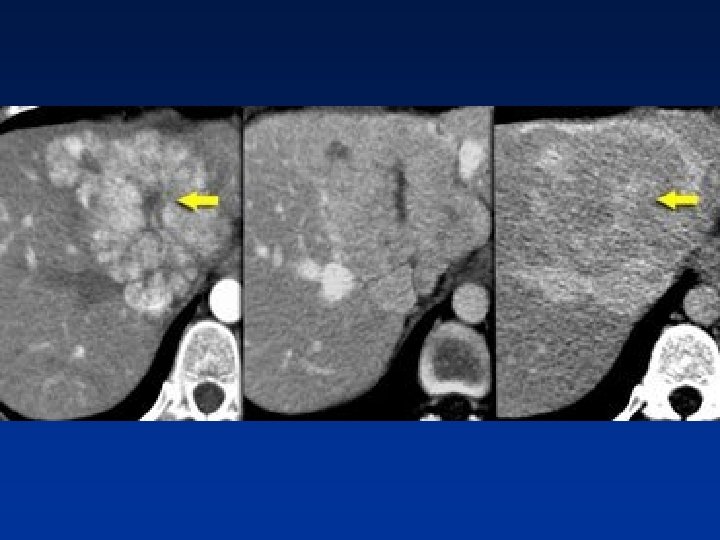

• Flash filling hemangioma in unenhanced, arterial & portal venous phase. Notice it matches the bloodpool.